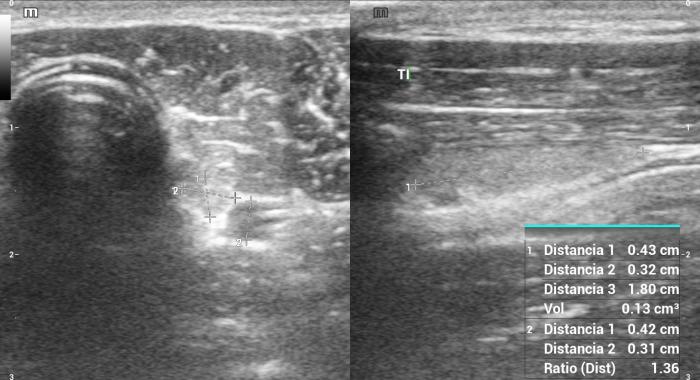

Relación entre el área transversal de la glándula tiroides (TG) y de la arteria carótida común (CCA)

El índice TG/CCA es una herramienta ecográfica cuantitativa propuesta para la evaluación del tamaño tiroideo en perros, particularmente útil cuando se sospecha de hipoplasia glandular o hipotiroidismo12. Este índice se calcula mediante la medición del área transversal del lóbulo tiroideo (TG) y la comparación con el área de la arteria carótida común (CCA) adyacente, ambas obtenidas en un corte transversal a nivel medio cervical8.

Para su obtención, el animal se posiciona en decúbito dorsal con el cuello extendido. Se utiliza un transductor lineal de alta frecuencia (mínimo 10 MHz), y se realiza una imagen transversal donde se identifican claramente el lóbulo tiroideo y la arteria carótida. Se mide el área de cada estructura mediante trazo elíptico o libre, dependiendo de la morfología. La relación se expresa como TG/CCA, un valor adimensional que permite estandarizar la evaluación tiroidea en animales de distinto tamaño corporal7.

En perros clínicamente sanos, se ha reportado un valor promedio de TG/CCA de 1.53 en promedio12. Valores consistentemente bajos pueden sugerir atrofia glandular o hipoplasia, siendo útiles para apoyar el diagnóstico de hipotiroidismo en pacientes con hallazgos clínicos y laboratoriales compatibles. Según Sasaki et al. (2020), si se utiliza el valor de corte <1.12, el índice TG/CCA indica hipotiroidismo con una sensibilidad del 100 %, una especificidad del 83 % y una precisión del 90 %.

Este índice se ha mostrado reproducible, poco afectado por el tamaño corporal o la edad, y puede ser una herramienta de utilidad en estudios longitudinales o de seguimiento terapéutico. Si bien su uso no reemplaza las pruebas hormonales específicas, constituye un complemento objetivo y no invasivo dentro del algoritmo diagnóstico ecográfico de la glándula tiroides en perros4.